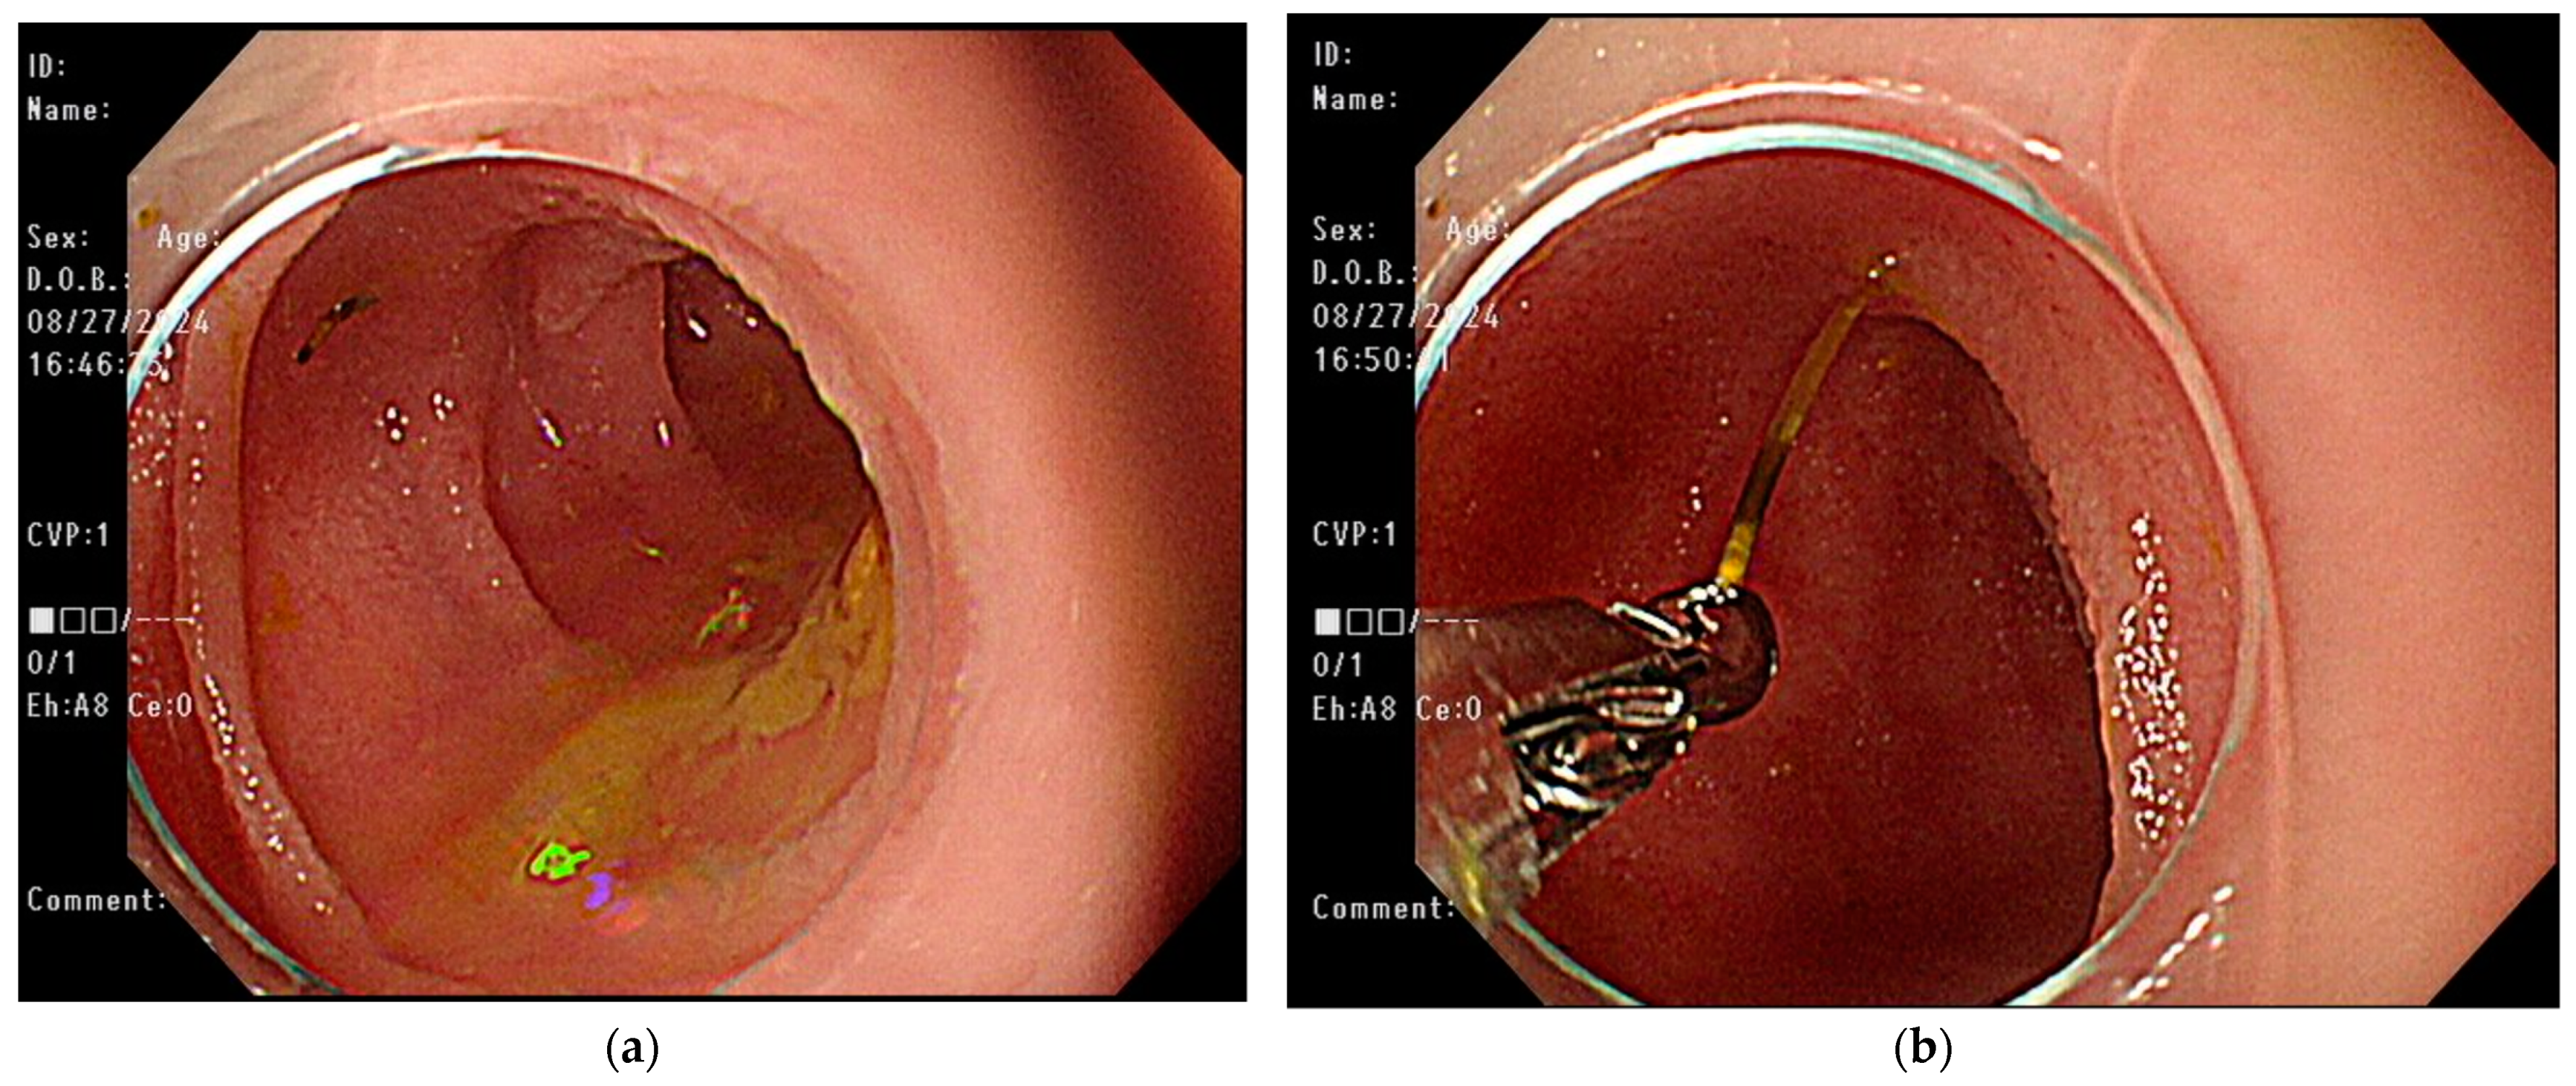

2. Case Presentation

| Our case | 51/F | Lower abdominal cramping pain, hematochezia | Distal ileum | Retrograde SBE with forceps | 2.3 cm | Resolution of symptoms |